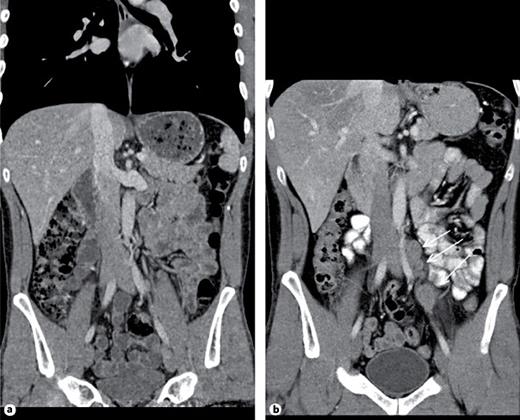

3rd patient: this 31-year-old patient underwent orchiectomy for testicular seminoma (pT3, CS1). Although markers were negative and no metastases were detected radiologically (Fig. 2a), the patient received adjuvant single-shot carboplatin therapy because of spermatic cord invasion of the primary and on grounds of personal choice of the patient. Twenty-six months thereafter he presented with a bulky retroperitoneal relapse (Fig. 2b). He was salvaged with 3 courses of BEP (bleomycin, etoposide and cisplatin) chemotherapy. It is to be noted here that the miR371a-3p level was at RQ = 3081.8 before orchiectomy and it continued to remain elevated at RQ = 351.8 five days after orchiectomy.

a Patient #3, left-sided testicular seminoma. Abdominal CT reveals unspecific small lymph node lateral to left iliac artery. Radiological diagnosis: no metastases detected. b Same patient, abdominal CT 26 months after adjuvant Carboplatin treatment: a chain of enlarged lymph nodes lateral to left iliac artery (arrows). Diagnosis: retroperitoneal relapse of seminoma.

Then, no further decrease was recorded. At the time of the clinically apparent relapse, the level had risen to RQ = 4240.3 and it decreased to normal levels at the completion of salvage therapy and remained stable during the later course. This case was briefly reported previously [13].